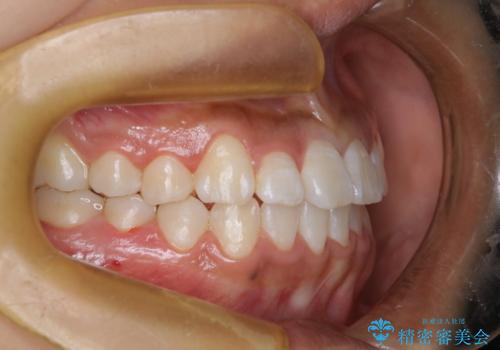

ワイヤー矯正で確実にガタつきを治したい セラミックブラケットによる治療

- 治療計画

- 前歯の叢生(がたつき)を主訴に来院された患者様です。以前マウスピース矯正をされていたそうでしたが、自身での継続が難しいことなどを理由に、ワイヤー矯正にて改めて矯正治療を希望されました。非抜歯にて治療を計画し治療を行いました。

歯の動きが良く、スムーズに治療を終了しました。一般的にワイヤー矯正はブラッシングが難しいのですが、毎回一生懸命セルフケアをされていたのが印象的です。治療においては、歯の衛生状態も一緒にチェック致します。